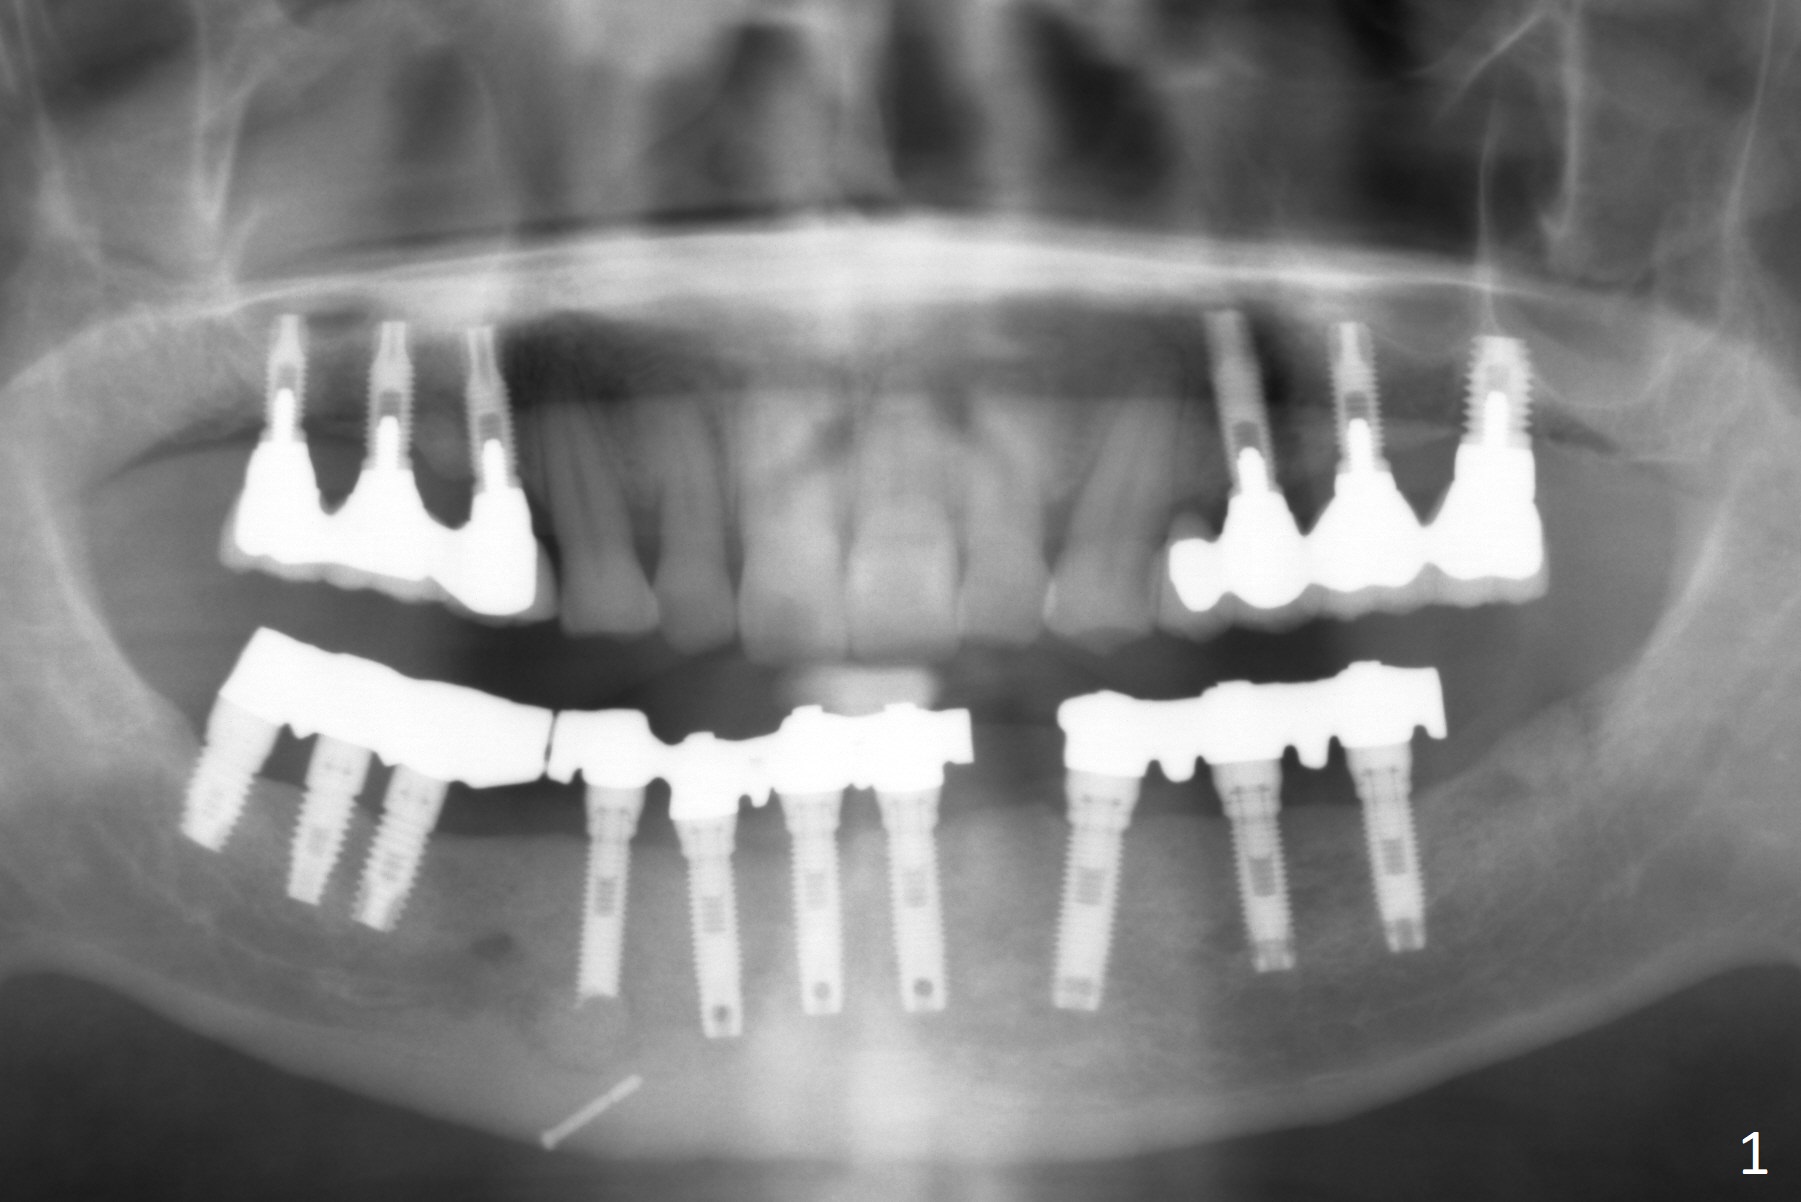

A 77-year-old man presents to clinic with chief complaint of loose lower denture, which is ~ 15 years old (Fig.1-6). The implants were placed ~ 30 years ago. There is wear and crack of the denture teeth (Fig.3). When the denture is remade, make metal occlusal surface at the premolar and molar region. An extra existing denture will be sent to lab for reference. What is the best method to take the lower impression? Block metal framework undercuts? Alginate or PVS?